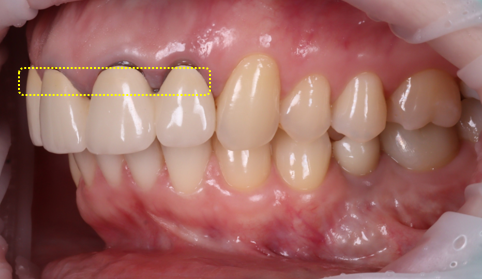

촬영 : 251030

최종적으로 완성된 지르코니아 크라운은 빛이 통과하면서 자연스러운 투명감이 느껴졌어요.

경계 부위가 검게 변해 있던 기존 모습이 생각나지 않을 정도로 큰 변화를 느낄 수 있었는데요.

환자분께서 거울을 보며 활짝 웃으셨던 순간이 아직도 기억납니다ㅎㅎ 개별 크라운으로 제작되어 치실 사용이 가능하여 사용법도 알려드렸습니다.

또한 잇몸 선도 시간이 지나며 점점 안정되기 때문에 시간이 지나면서 더 자연스러워질 거라고 설명을 드렸죠ㅎㅎ

틀어진 치아 축도 얼굴 앞면을 바라보도록 제작했죠.